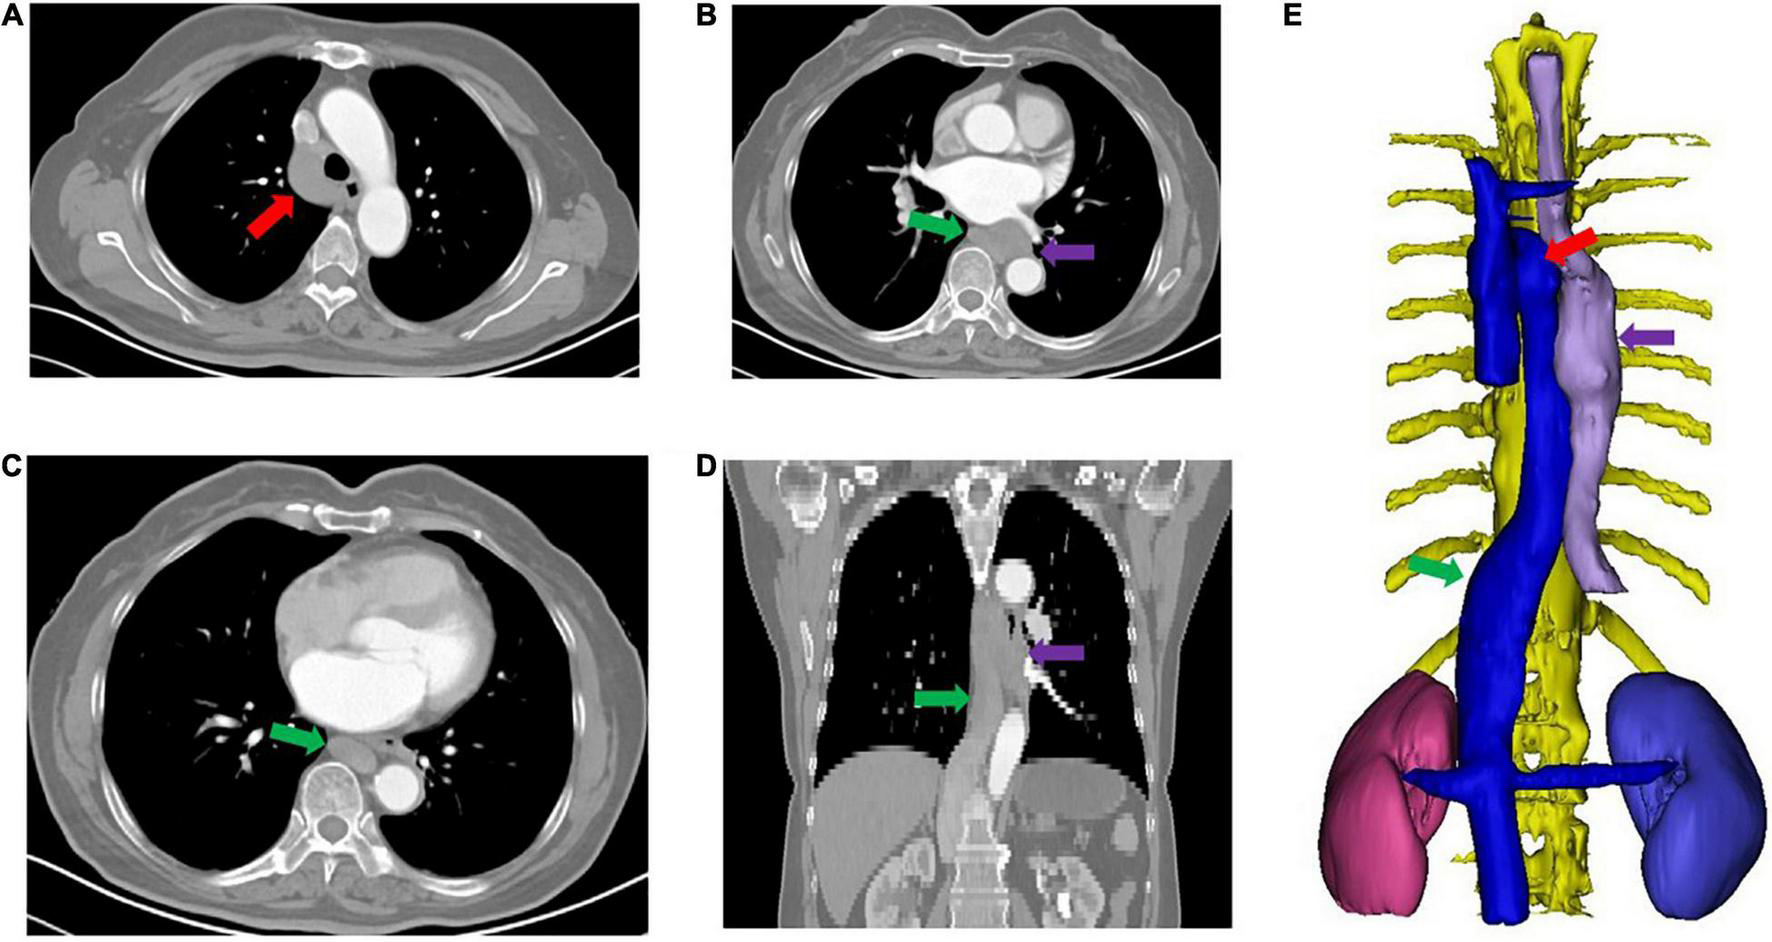

FIGURE 1

CT reconstruction showing azygos continuation of the inferior vena cava (not preoperatively recognized). (A–D) Show the enlarged arch of the azygos vein and azygos vein. (E) Shows hepatic segment absence of the inferior vena cava with azygos continuation. The red arrow shows the enlarged arch of the azygos vein; the green arrow shows the azygos vein; the purple arrow shows the tumor.